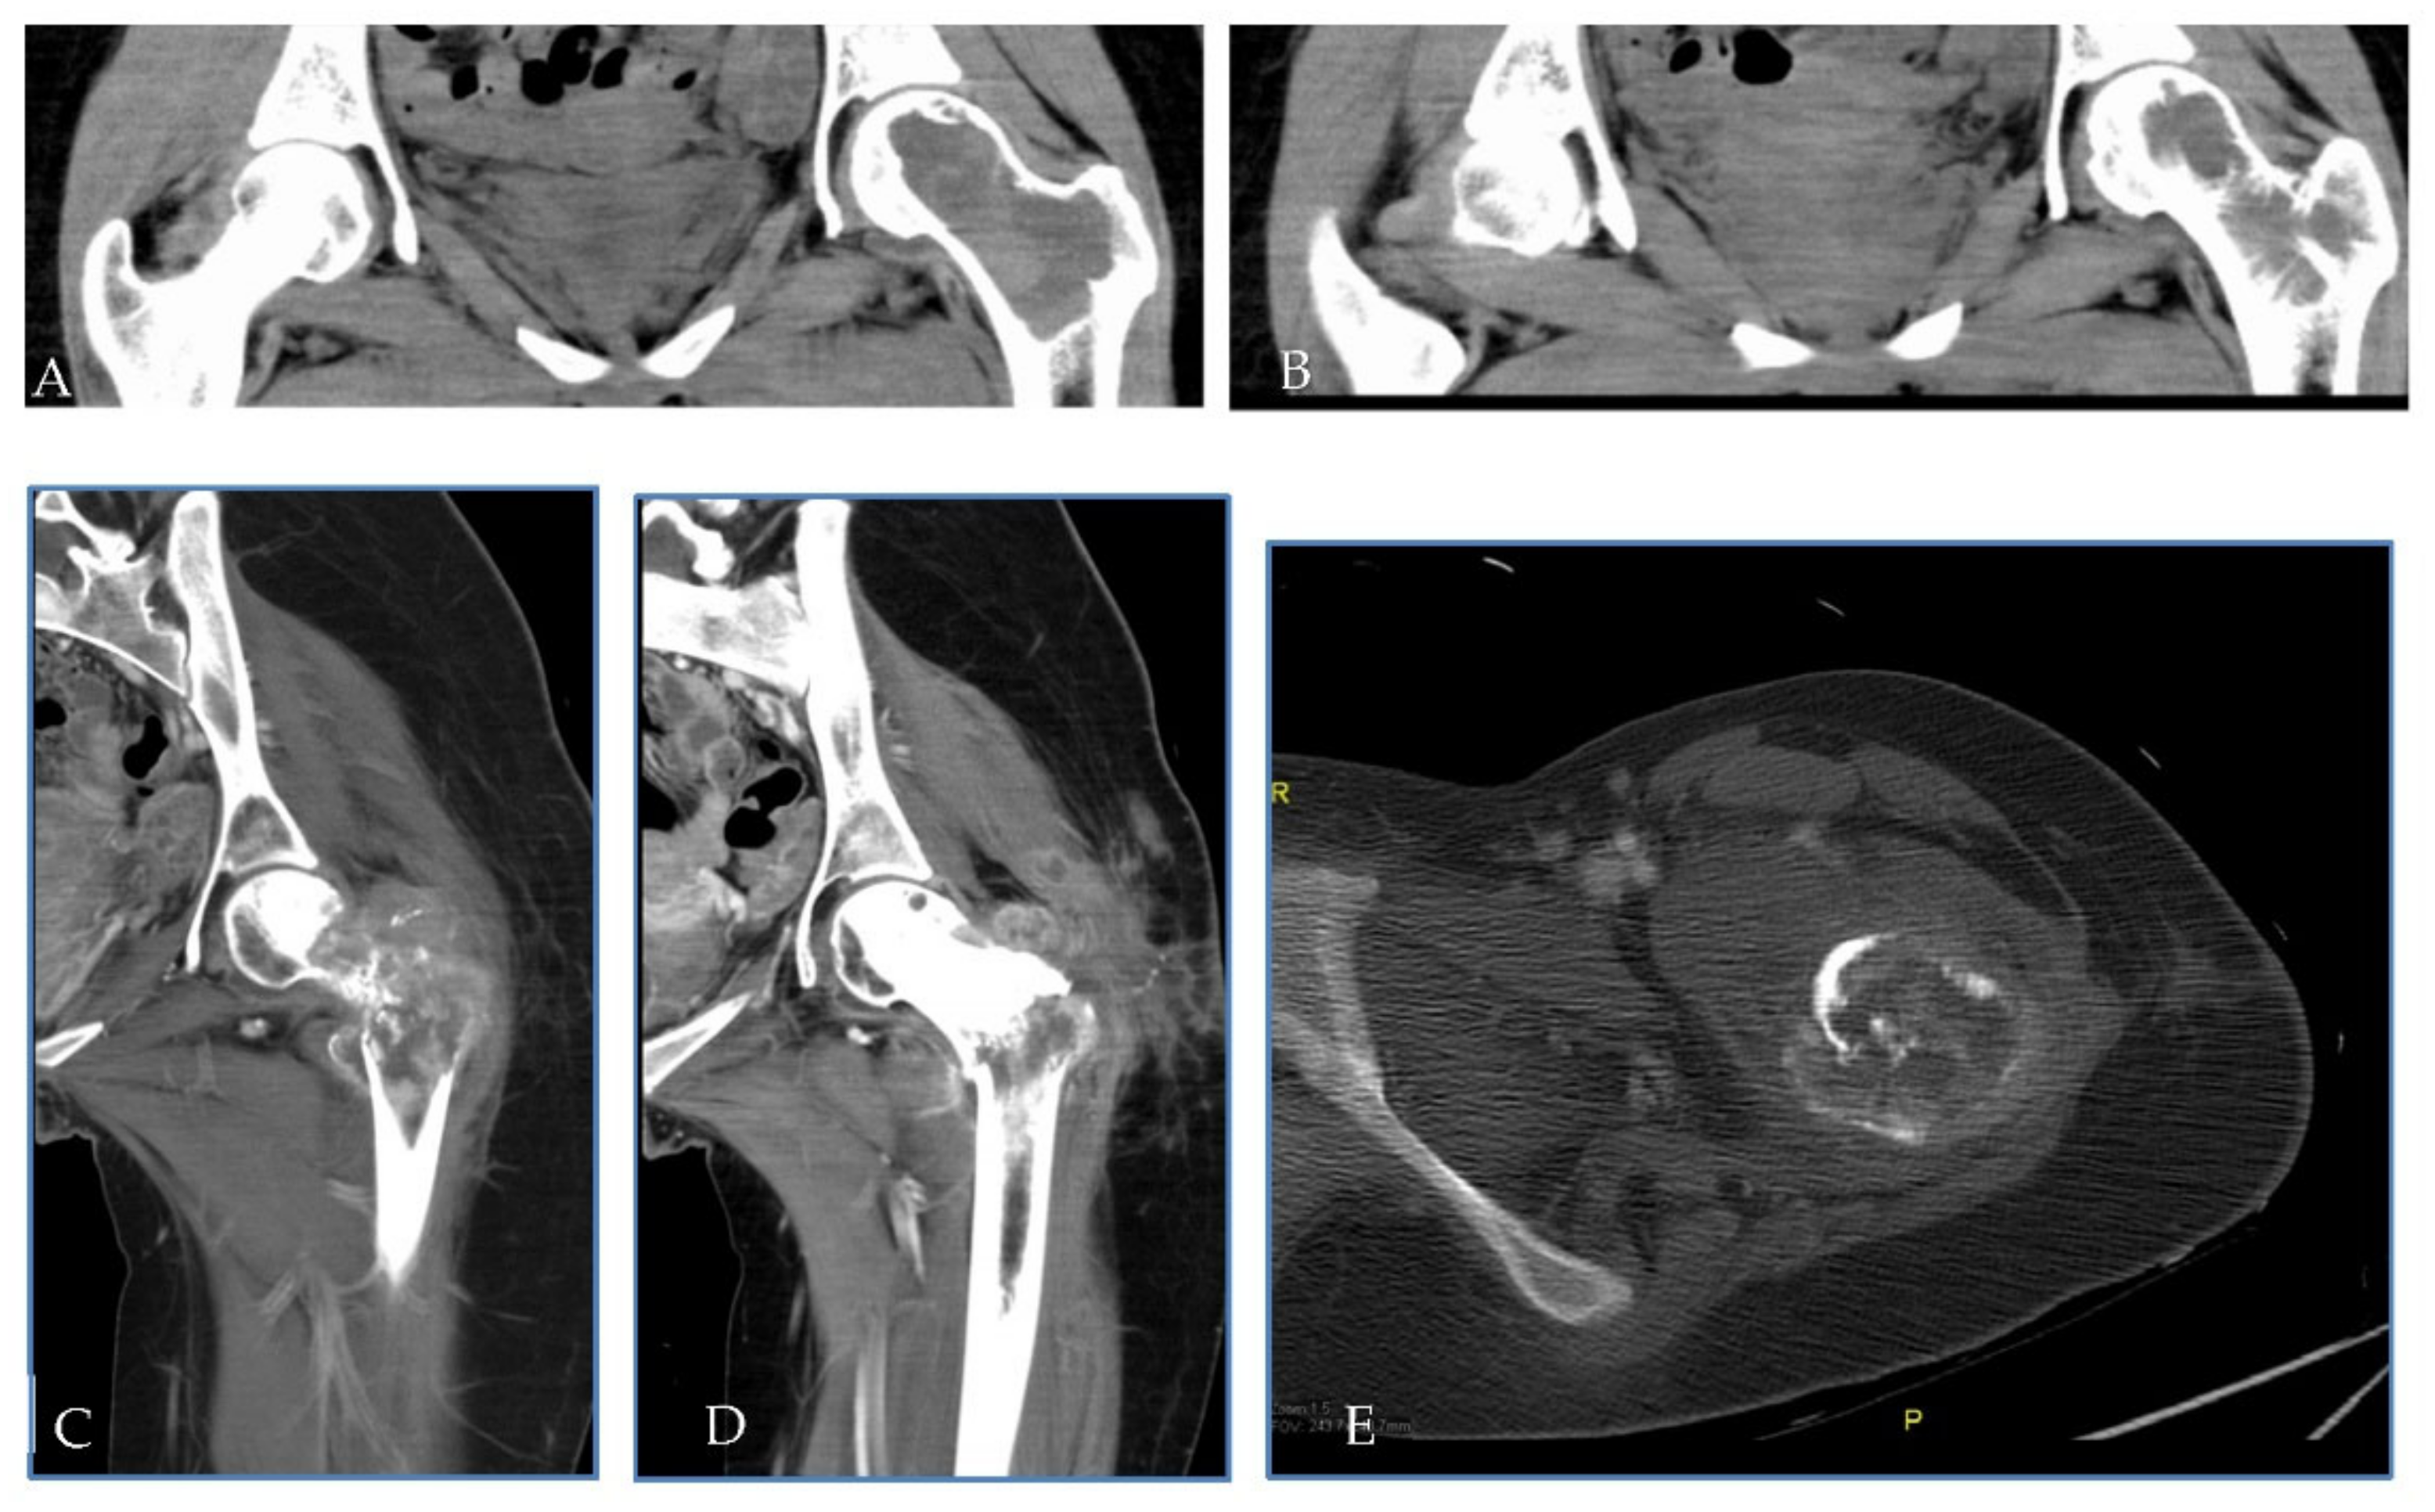

2.1. Patient 1

2.2. Patient 2

2.3. Patient 3

| Age | Sex | ECOG PS | Diagnosis (Date) | Site of Primary GCTB | Surgery | Rec. Date | Treat. Management | Malignant Transformation (Date/Surgery or Biopsy) | Treat. | Evolution | Subsequent CHT Lines | FU/D | Time to MT (Months) | OS from GCTB Diagnosis (Months) | OS from MT (Months) | |

|---|---|---|---|---|---|---|---|---|---|---|---|---|---|---|---|---|

| Pt 1 | 29 | F | 0 | 17 July | Right femur | Curettage and bone grafts | 18 February | Neoadj denosumab (7 cycles) | 18 July Extraarticular resection: high-grade fibroblastic osteosarcoma | ISG/OS-2 | PD | I: IFO II: GEM.TXT III: PAZO | D 22 January | 9 | 53 | 43 |

| Pt 2 | 48 | M | 0 | 16 November | Right tibia | Curettage and bone grafts | 20 October | Neoadj denosumab (6 cycles) | 21 February Extraarticular resection: malignant transformation of GCTB | EURO BOSS | NED | - | FU 21 December | 51 | 64 | 13 |

| Pt 3 | 20 | F | 0 | 10 September | Left femur | Resection of the femoral head, curettage and bone grafts | 11 March | Biopsy | 11 June Biopsy: high-grade osteosarcoma G3 with aberrant expression of beta-HCG | ISG/OS-1 | PD | - | D 11 November | 9 | 14 | 5 |